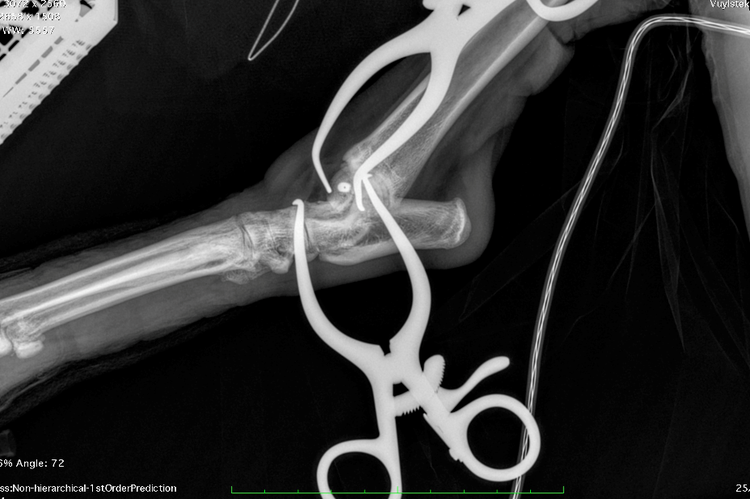

The fracture’s small size, delicate location, and proximity to the joint meant precision was critical. To ensure accurate screw placement, Mark performed the surgery under real-time intra-operative imaging - a technique he has refined over more than a decade. Using continuous X-ray guidance allowed confirmation of ideal screw trajectory and depth, avoiding both joint violation and inadequate fracture engagement.